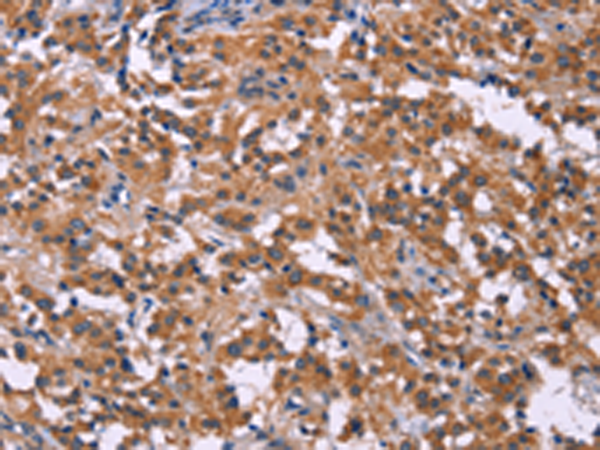

分类: 科研抗体货号: P08018别名: MSS4; STM7应用: IHC反应种属: Human, Mouse, Rat